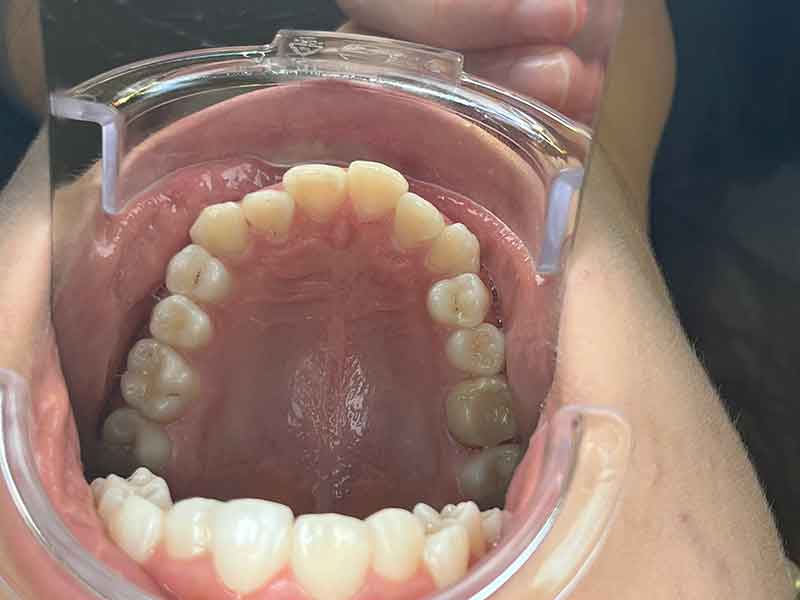

Situation initiale · Juin 2024

Quand les parents de cette jeune patiente de 13 ans consultent OrthoLight, la question n'est pas évidente à formuler : les dents ne semblent pas si mal alignées de face, mais quelque chose ne va pas. C'est en vue latérale que la situation apparaît clairement — et qu'elle justifie d'agir maintenant.

La vue latérale droite est très parlante. Le praticien observe deux problèmes liés :

Une canine supérieure proéminente

Elle ne s'inscrit pas harmonieusement dans l'arcade. Ce signe révèle un manque de place transversal : le maxillaire n'a pas suffisamment grandi en largeur, créant à la fois cet encombrement et le décalage entre les arcades.

Les deux problèmes ont une cause commune : l'arcade supérieure est trop étroite. C'est sur elle que le traitement va agir directement.

Face à ce tableau clinique, OrthoLight choisit une plaque d'expansion palatine — un appareil amovible fabriqué sur mesure à partir d'une empreinte de l'arcade supérieure. Ce n'est pas un appareil fixe. C'est une intervention légère, précise, et parfaitement adaptée à la fenêtre de croissance de cette patiente.

Comment fonctionne la plaque d'expansion

L'appareil se compose d'une base en résine qui recouvre le palais, de crochets qui s'accrochent aux dents pour maintenir l'appareil en place, et d'une vis centrale. Cette vis, activée régulièrement à la maison selon un protocole précis, est le cœur du mécanisme.

En s'ouvrant progressivement, elle exerce une pression latérale douce et constante sur les deux moitiés du palais. Cette pression stimule la suture palatine médiane et provoque une expansion osseuse progressive. Ce n'est pas une force mécanique brutale : c'est une stimulation biologique qui accompagne la croissance dans la bonne direction.

Le résultat : le maxillaire s'élargit, l'arcade gagne en largeur, les dents disposent de plus d'espace pour s'aligner. Et en corrigeant la largeur de l'arcade supérieure, on améliore mécaniquement la relation entre les deux mâchoires — ce qui réduit directement le décalage de Classe II.